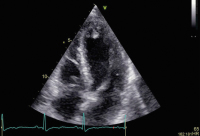

Fallbericht: Tako-Tsubo-Syndrom: Thromboembolierisiko in der Frühphase vielleicht unterschätzt?

Journal für Kardiologie - Austrian Journal of Cardiology 2020; 27 (9-10): 344-345 Volltext (PDF) Abbildungen mit Filmsequenzen